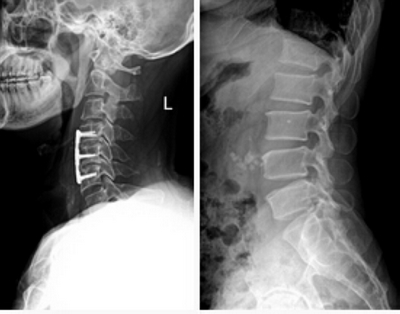

1. 數字化攝影

★適用于全身各部位攝影,包括常規攝影(立位攝影、臥位攝影等,如胸片、頸椎、腰椎、腹部、頭顱、四肢等)和特殊攝影(傾斜攝影、角度攝影等,如瓦氏位、骶髂關節、髕骨軸位、跟骨軸位等)。